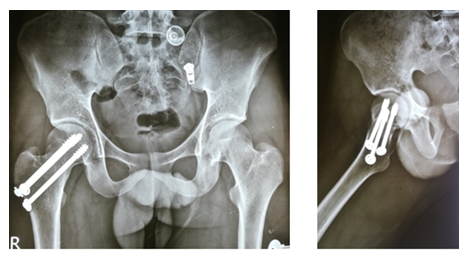

After selecting a case according to inclusion and exclusion criteria, patients were evaluated preoperatively. An elaborate history was taken. This was followed by a general examination and local examination. After admission, patients were put on surface traction to the affected limb with 1/10th of the patient's body weight. All patients underwent preoperative counselling regarding the operative procedure, probable complications, outcome, and other treatment options, along with their merits and demerits. After being informed, written consent was obtained. After preparing the patients for operation, Closed reduction is performed with the patient in the supine position on a fracture table (Figure 1). Reduction was confirmed by C-arm. After reduction, three guide wires are placed, usually in an inverted triangular fashion (Figure 2).

The screw lengths are measured, and drilling is performed using a 4.5 mm cannulated reamer. The screws are then inserted (for the BDSF technique, a specific sequence of middle, then superior, and lastly inferior screw insertion is to be followed). All three screws are inserted less than 5 mm subchondrally (Figure 3,4). In all cases, a prophylactic antibiotic was given. In the postoperative ward, proper fluid and hemodynamic balance were ensured. Change of posture was done twice an hour. The antibiotic was continued for 3 days. Analgesics were given to ensure a pain-free postoperative period. On the first postoperative day, patients were allowed to sit on the side of the bed. Patients were being educated about breathing exercises, isometric quadriceps exercises, gluteal exercises, and ankle pumping exercises. An immediate postoperative X-ray was done (Figure 5). After checking the dressing, on 4th POD, they were discharged from the hospital if their postoperative period was uneventful. Oral antibiotics were given for 10 days. Advice was given to continue isometric quadriceps exercise. Regarding ambulation, they were advised to do non-weight-bearing (of the affected side) crutch ambulation until directed by the physician. Use of elevated toilet seats onwards is also advised. The next follow-up would be given at the 14th POD. The first follow-up was given at 14th POD to check any signs of infection, pain status, and distal neurovascular status. The stitch was removed on the same day. Advice given about isometric quadriceps exercise, active abduction, extension exercise, and stretching exercise of the hip joint. The next follow-up was the 6th week after the operation. The range of motion was tested. An X-ray was done to check callus formation. Improvements were noted. Partial weight bearing was given at this follow-up. Subsequent follow-up was given at 12 weeks and every 4 weeks until union has been achieved or at least 9 months (Figures 6-10).